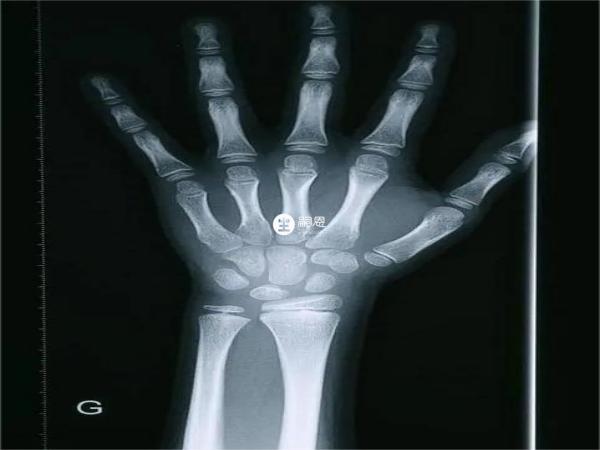

骨質的生長主要就是從骨骺部位轉移而來,所以只有骨骺未閉合的時候骨質才能不斷進行生長,閉合之後就不會再增長。

女性的身高如果停止長高,一般有骨骺線完全閉合的跡象,這個情況可以通過B超檢驗出來,另外月經來潮也說明女生停止長高了,黃體生成素和卵泡刺激素作用於卵巢,卵巢分泌雌激素,對雌激素敏感的器官加快生長,骨骺會逐漸閉合。